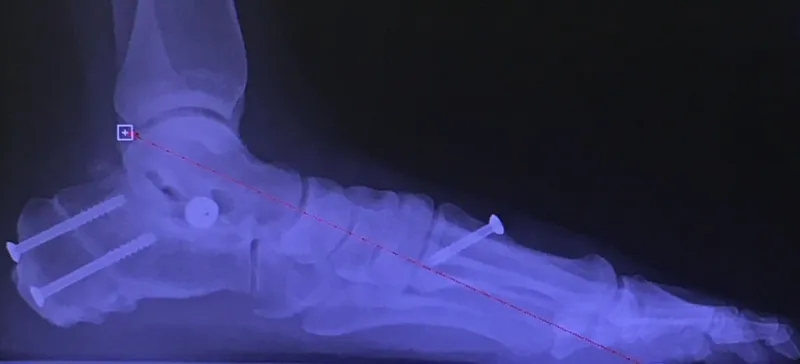

Pre-operative x-rays of the flatfoot with the talus deviated medially due to subluxing off the calcaneus causing the midtarsal joint to sublux laterally and uncovering of the talar head at the talo-navicular joint (left). The talus bone should line up with or be close to paralletl with a line drawn through the 1st metatarsal shaft (right). This is referred to as Meary's angle.

One case see an improvement in Meary's angle after surgical repair of the flatfoot with a subtalar joint implant which blocks the subluxation of the talus off of the calcaneus.

Below are x-rays of a foot pre-operatively (left) where the black line indicates and plantarflexed (downward directed) talus bone and post-surgical repair with a subtalar joint implant and lenthening of the calf muscle which allows the calcaneus (heel bone) to set underneath the talus and the implant keeps the talus from subluxing off the calcaneus and now the talus is more inline with the front of the foot (right).